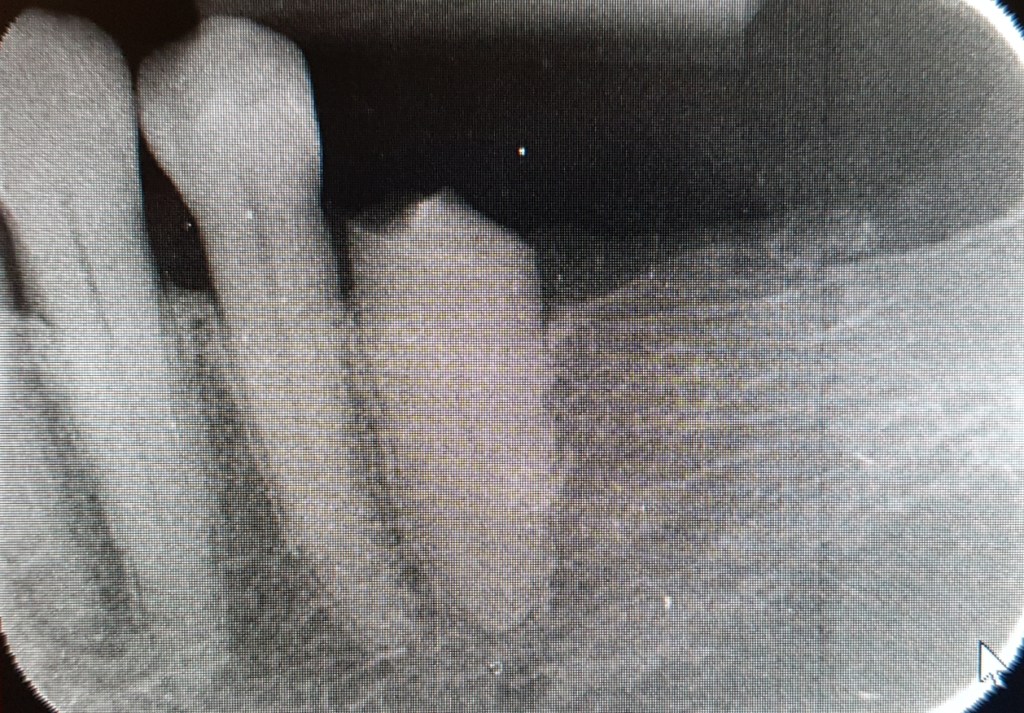

A fenti esetben a páciens nem is reménykedett letört fogának megmentésében és foghúzásra kért időpontot. Mivel azonban a törés, szerencsésen az ínyszint felett történt, gyökérkezeléssel és csapos megerősítéssel a fog megmentése mellett döntöttünk.

A gyökércsatornába beragasztott csap lehetőséget teremtett a fog koronázására, ám statikai okból a szomszédos fogra is korona készült.